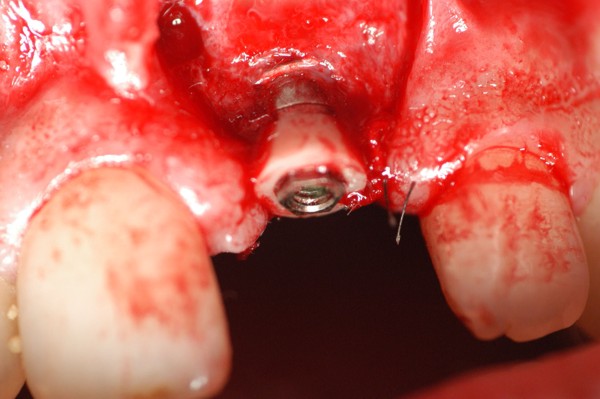

Abstract: Las fuerzas anterógradas traumáticas son en general las causantes de fracturas radiculares en el sector anterior de la boca. Desarrollo: El paciente se presenta a la consulta , con la fractura de una funda de porcelana inyectada en la zona cérvico palatina, solicitando simplemente la reparación en boca para evitar rozamientos linguales. Dicha funda con un perno colado en oro y su correspondiente endodoncia, habían sido realizadas en mi clínica varios años atrás, con un «aparente éxito total». Radiograficamente, se encuentra una fractura radicular cercana al tercio gingival Observada la oclusión de las piezas anteriores, podemos ver que el vínculo ideal de Acoplamiento, no se cumple, habiendo una relación de franco contacto la que ha provocado la fractura. Llevando al paciente a Oclusión en Relación Céntrica, podemos ver el espacio a nivel anterior, correspondiente a la centricidad mandibular. En esa misma posición , es dable percibir una faceta parafuncional mesial del primer premolar superior… …que antagoniza con una faceta parafuncional distal del canino inferior… ..constituyendo un plano inclinado que provoca la antelación mandibular o Discrepancia Horizontal, fracturando la raiz del incisivo central. Extraida la porción coronal de la raiz, pensamos en la realización de un Implante Inmediato, a pesar de la presencia de una fístula dado que se trataba de un central, decisión que obtuvo éxito implantario mas no estético, según veremos luego. Era fundamental conservar lo mas posible las tablas óseas, que de hecho había perdido la porción cervical Realizamos una incisión que conservara las papilas de las piezas adyacentes. Realizamos la exodoncia mediante un instrumento construido «ad hoc» que denomino: Con lo que obtenemos la preservación «ad integrum» de las corticales peridentarias remanentes. Instalamos entonces un implante T.B.R. de 15 mm de largo por 4 mm de diam. con cuello de zirconio de 3,5 mm …quedando tres espiras sin hueso por vestibular, producto de la tabla perdida, Incidimos el periostio a nivel apical del colgajo para obtener mayor paño quirúrgico, y legramos un bolsillo palatino sin incisiones de descarga, para la inserción de la membrana. Suplementamos la carencia ósea vestibular con «BIOSS» …e instalamos una membrana reabsorbible «BIOGUIDE» , que fijamos con el mismo implante, y calzamos por palatino. Suturamos Instalamos nuestra provisional previamente confeccionada, sobre un abuttment de titanio. Y controlamos radiograficamente Pasadas tres semanas del retiro de los puntos, observamos una cicatrización alta que nos muestra el anillo de zirconio del implante. ……………………………………………….. Transcurridos tres meses preparamos una nueva cirugía, dirigida a instalar un injerto autólogo de conectivo en el área del anillo, con un nuevo desplazamiento del colgajo vestibular. Tomamos tejido conectivo del paladar a nivel de los premolares, mediante una incisión mucosa «en libro», y disección del conectivo subyacente. Lo posicionamos en vestibular del anillo de zirconio y lo fijamos mediante sutura Y semanas después nos encontramos con un nuevo fracaso de orden estético. ……………………………………………….. En la actualidad, el caso esta estable , aún con su funda provisional, a la espera de un nuevo intento plástico, mediante Injerto Libre de Encia. ………………………………………………….. ESQUEMA MECÁNICO DEL FENÓMENO …que además de los hechos mostrados en el caso presentado, frecuentemente provocan en el sentido antero posterior los fenómenos de DISPERSIÓN ,en el maxilar superior…y de APIÑAMIENTO en el maxilar inferior. CONCLUSIONES: Además del rigor académico que nos convoca… esta; nuestra casa…nos otorga la confianza que solo da el saber que estamos siempre entre amigos, que cada vez son más. Por tanto es que debo decir: YO fui el responsable de dicha fractura… …porque… …..que hubiera sucedido si hubiera hecho todo el trabajo implantario sin ajustar previamente su oclusión? Seguramente a esta altura del caso…también hubiera fracasado el implante. Siempre decimos que se aprende de los errores más que de los aciertos, y Dr. Carlos A. Acuña Priano

Fig.18(Pie de foto: Instalación de Implante)

Fig .19(Pie de foto: espiras al descubierto)

Fig.20(Pie de foto: Incisión del periostio)

Fig.21(Pie de foto: injerto aloplástico )

Fig.22(Pie de foto: Membrana)